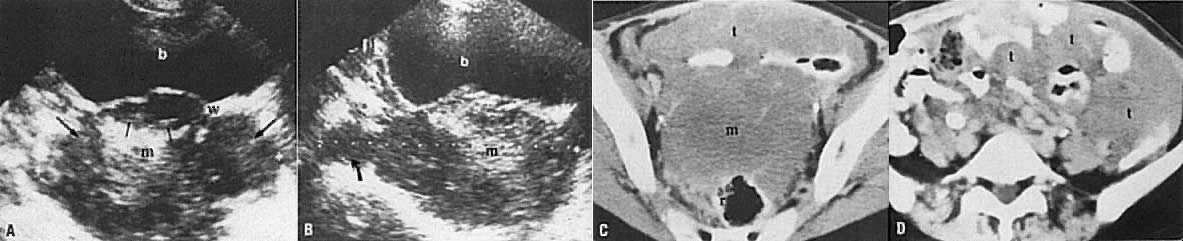

Leiomyosarcomas constitute 3% of uterine body tumors. They are very invasive neoplasms that frequently present at an advanced stage. The typical ultrasound appearance is that of a very irregular mass with bizarre areas of degeneration, high-level echoes, and invasion of the surrounding pelvic structures (Fig. 24A and B).52 CT shows a large, irregular uterine tumor with invasion of the surrounding pelvic organs, peritoneum, and omentum (Fig. 24C and D).

Fig. 24. Stage IV leiomyosarcoma of the uterus. Transverse ( A) and sagittal ( B) sonograms of the uterus show it to be replaced by a large, inhomogeneous solid mass ( m) with high- and medium-level echogenicity. There is evidence of extension superiorly ( curved arrow) and into the parametria ( long arrows) and bladder ( short arrows ). Serial CT scans of the pelvis ( C and D) show a large mass ( m) that is seen to spread to the mesentery ( t ). The perirectal fat plane is also obliterated, which is consistent with rectal invasion. ( r, rectum; w, bladder wall; b, bladder.)